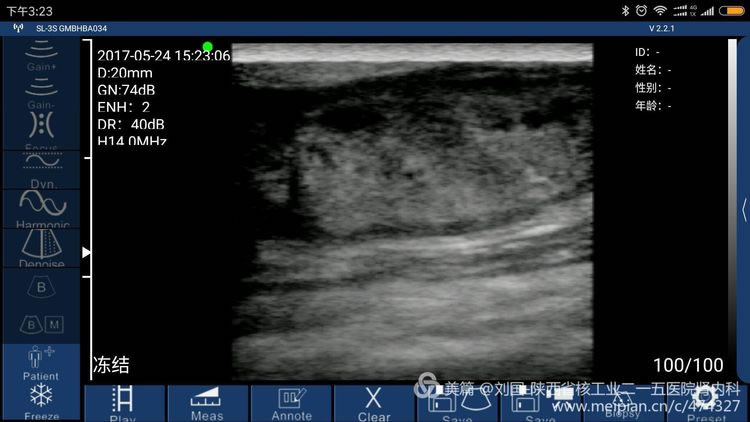

Result checked by Sonostar’s wireless ultrasound, and displayed by my mobile phone-Mi max

Cephalic vein condition checked by Sonostar’s wireless ultrasound, and displayed by my mobile phone-Mi max